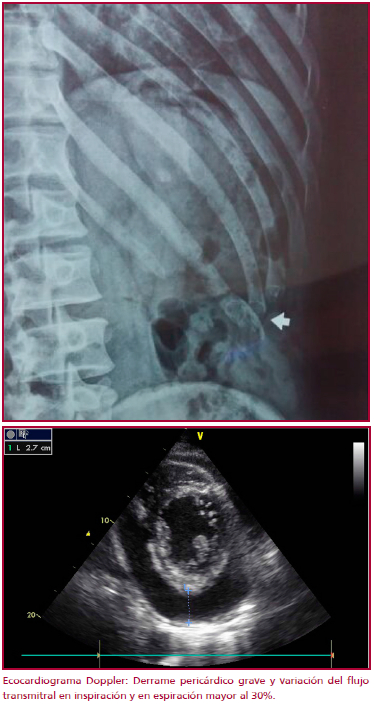

Placa de tórax: fractura 11 costilla izquierda (Figura 1).

Debido a la presencia de derrame pericárdico grave asociado a la progresión de los síntomas, se realizó una pericardiocentesis; se informó la presencia de líquido de aspecto turbio, color rojizo sanguinolento, con abundantes glóbulos rojos, leucocitos 210 células/mm3 (neutrófilos 60%, linfocitos 40%), PH: 7,5, proteínas: 3,9 g%, glucosa: 1,33 g/l, ácido úrico: 2,8 mg/dl, LDH: 1 347 UI/l. Cultivo para gérmenes comunes, BAAR y hongos: negativos. Perfil autoinmune negativo. Anatomía patológica sin evidencia de células neoplásicas.

Se realizó un ecocardiograma de control, que evidenció mínimo líquido en pericardio y ausencia de variaciones inspiración/espiración en el flujo transmitral.